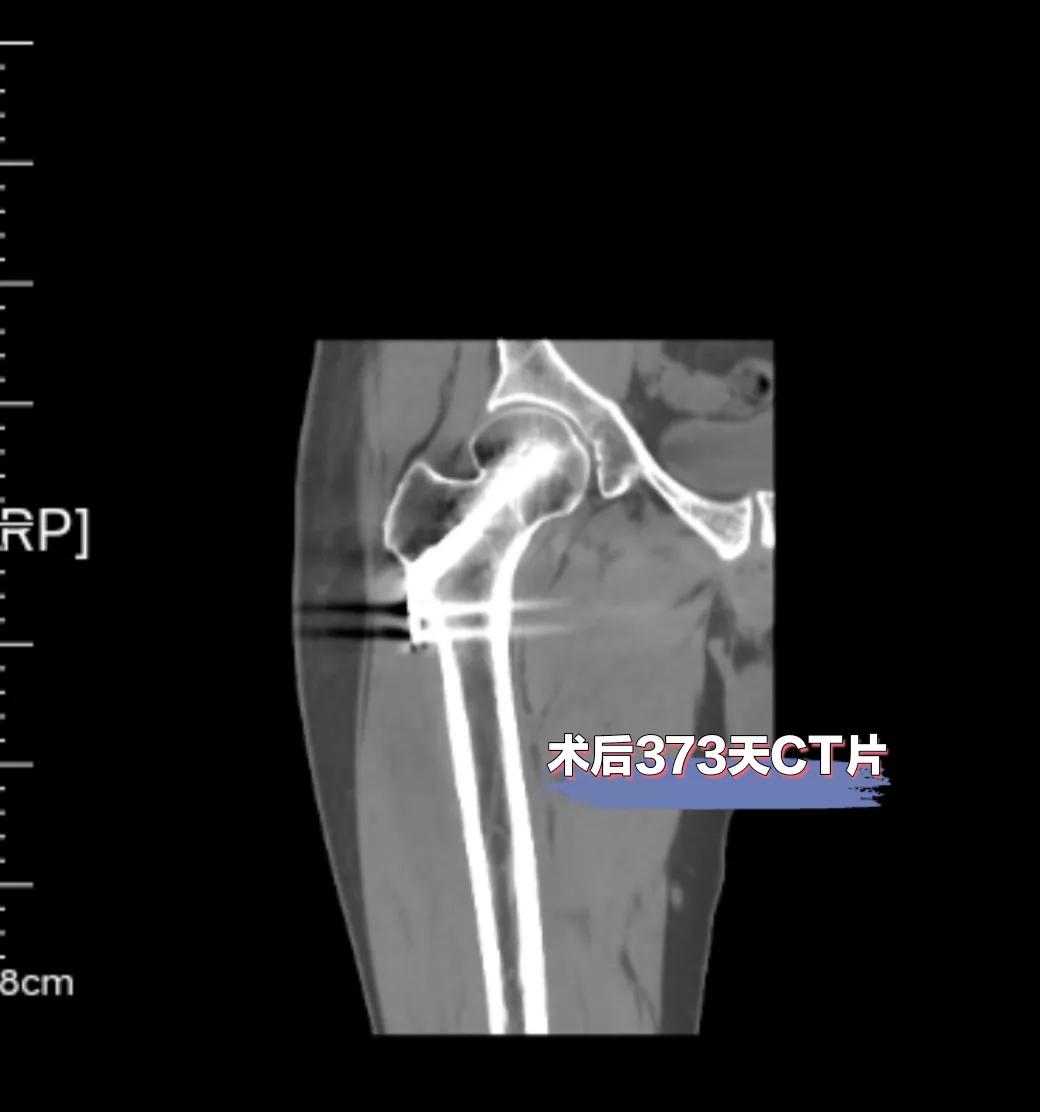

最后,附上我脱拐后复查的片子(图7,8,9),目前一切正常!已经正常上班,正常生活,希望能闯过2年高危期!加油吧,折友们!

图7

图8

图9